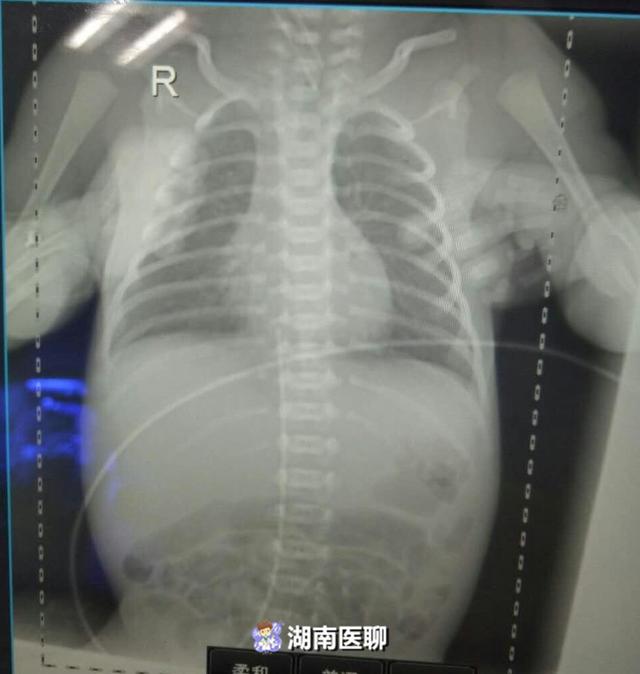

9月2日,一名孕28周宝宝由一县医院急诊宫内转运到湘南学院附属医院,9月6日,体重只有1.1kg的宝宝由产科转入新生儿科。

因为过早出生,宝宝多器官功能发育不全,患有新生儿肺透明膜病、新生儿感染等,抵抗力低,救治过程中需要闯过很多道关卡,孩子需要气管插管有创呼吸机辅助通气给氧,不可避免的问题就是要通过静脉输入各种药物,包括抢救、抗感染及氨基酸及脂肪乳等各种药物。

而对于一个孕28周出生体重仅1.1kg的早产儿宝宝来说,皮肤娇嫩,血管既细又脆,外周静脉用药难度非常大,需要从脐静脉置管输入药物。

新生儿复苏、早产儿尤其是极低出生体重儿的救治过程中,静脉通路的建立十分重要,也是一大难点。新生儿脐静脉置管术是利用新生儿脐静脉,为新生儿静脉通路搭建了一个重要途径,通过脐静脉导管注射药物、静脉营养,最多可留置10~14天。

俗话说,新生儿科医师就像“绣花姑娘”。作为近年发展起来的一种新技术,脐静脉置管技术难度确实非常大的。首先脐静脉导管的插入,必须顺着静脉走向螺旋式插入,稍有不慎导管就有可能进入肝血管,要将绣花针一样细的导管末端准确放置在准确的位置,这就要求穿刺前要经过仔细测量,精确导管长度,以及过硬的操作技术,没有一定水平的医务人员,一般都不敢贸然操作。

就在宝宝入院当天,在邝爱玲主任、刘刚主治医生、李卫萍护士的强强联手下,成功为宝宝置入脐静脉导管,并顺利输入静脉营养液,重新为宝宝搭建了“生命之桥”。